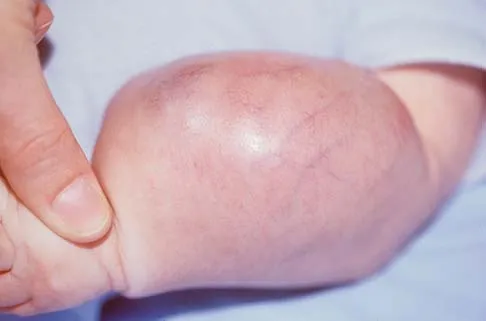

An infant is born with a mass that involves both the volar and dorsal compartments of the left arm. A clinical photograph and biopsy specimen are shown in Figures 41a and 41b. What is the best initial course of action?

Explanation